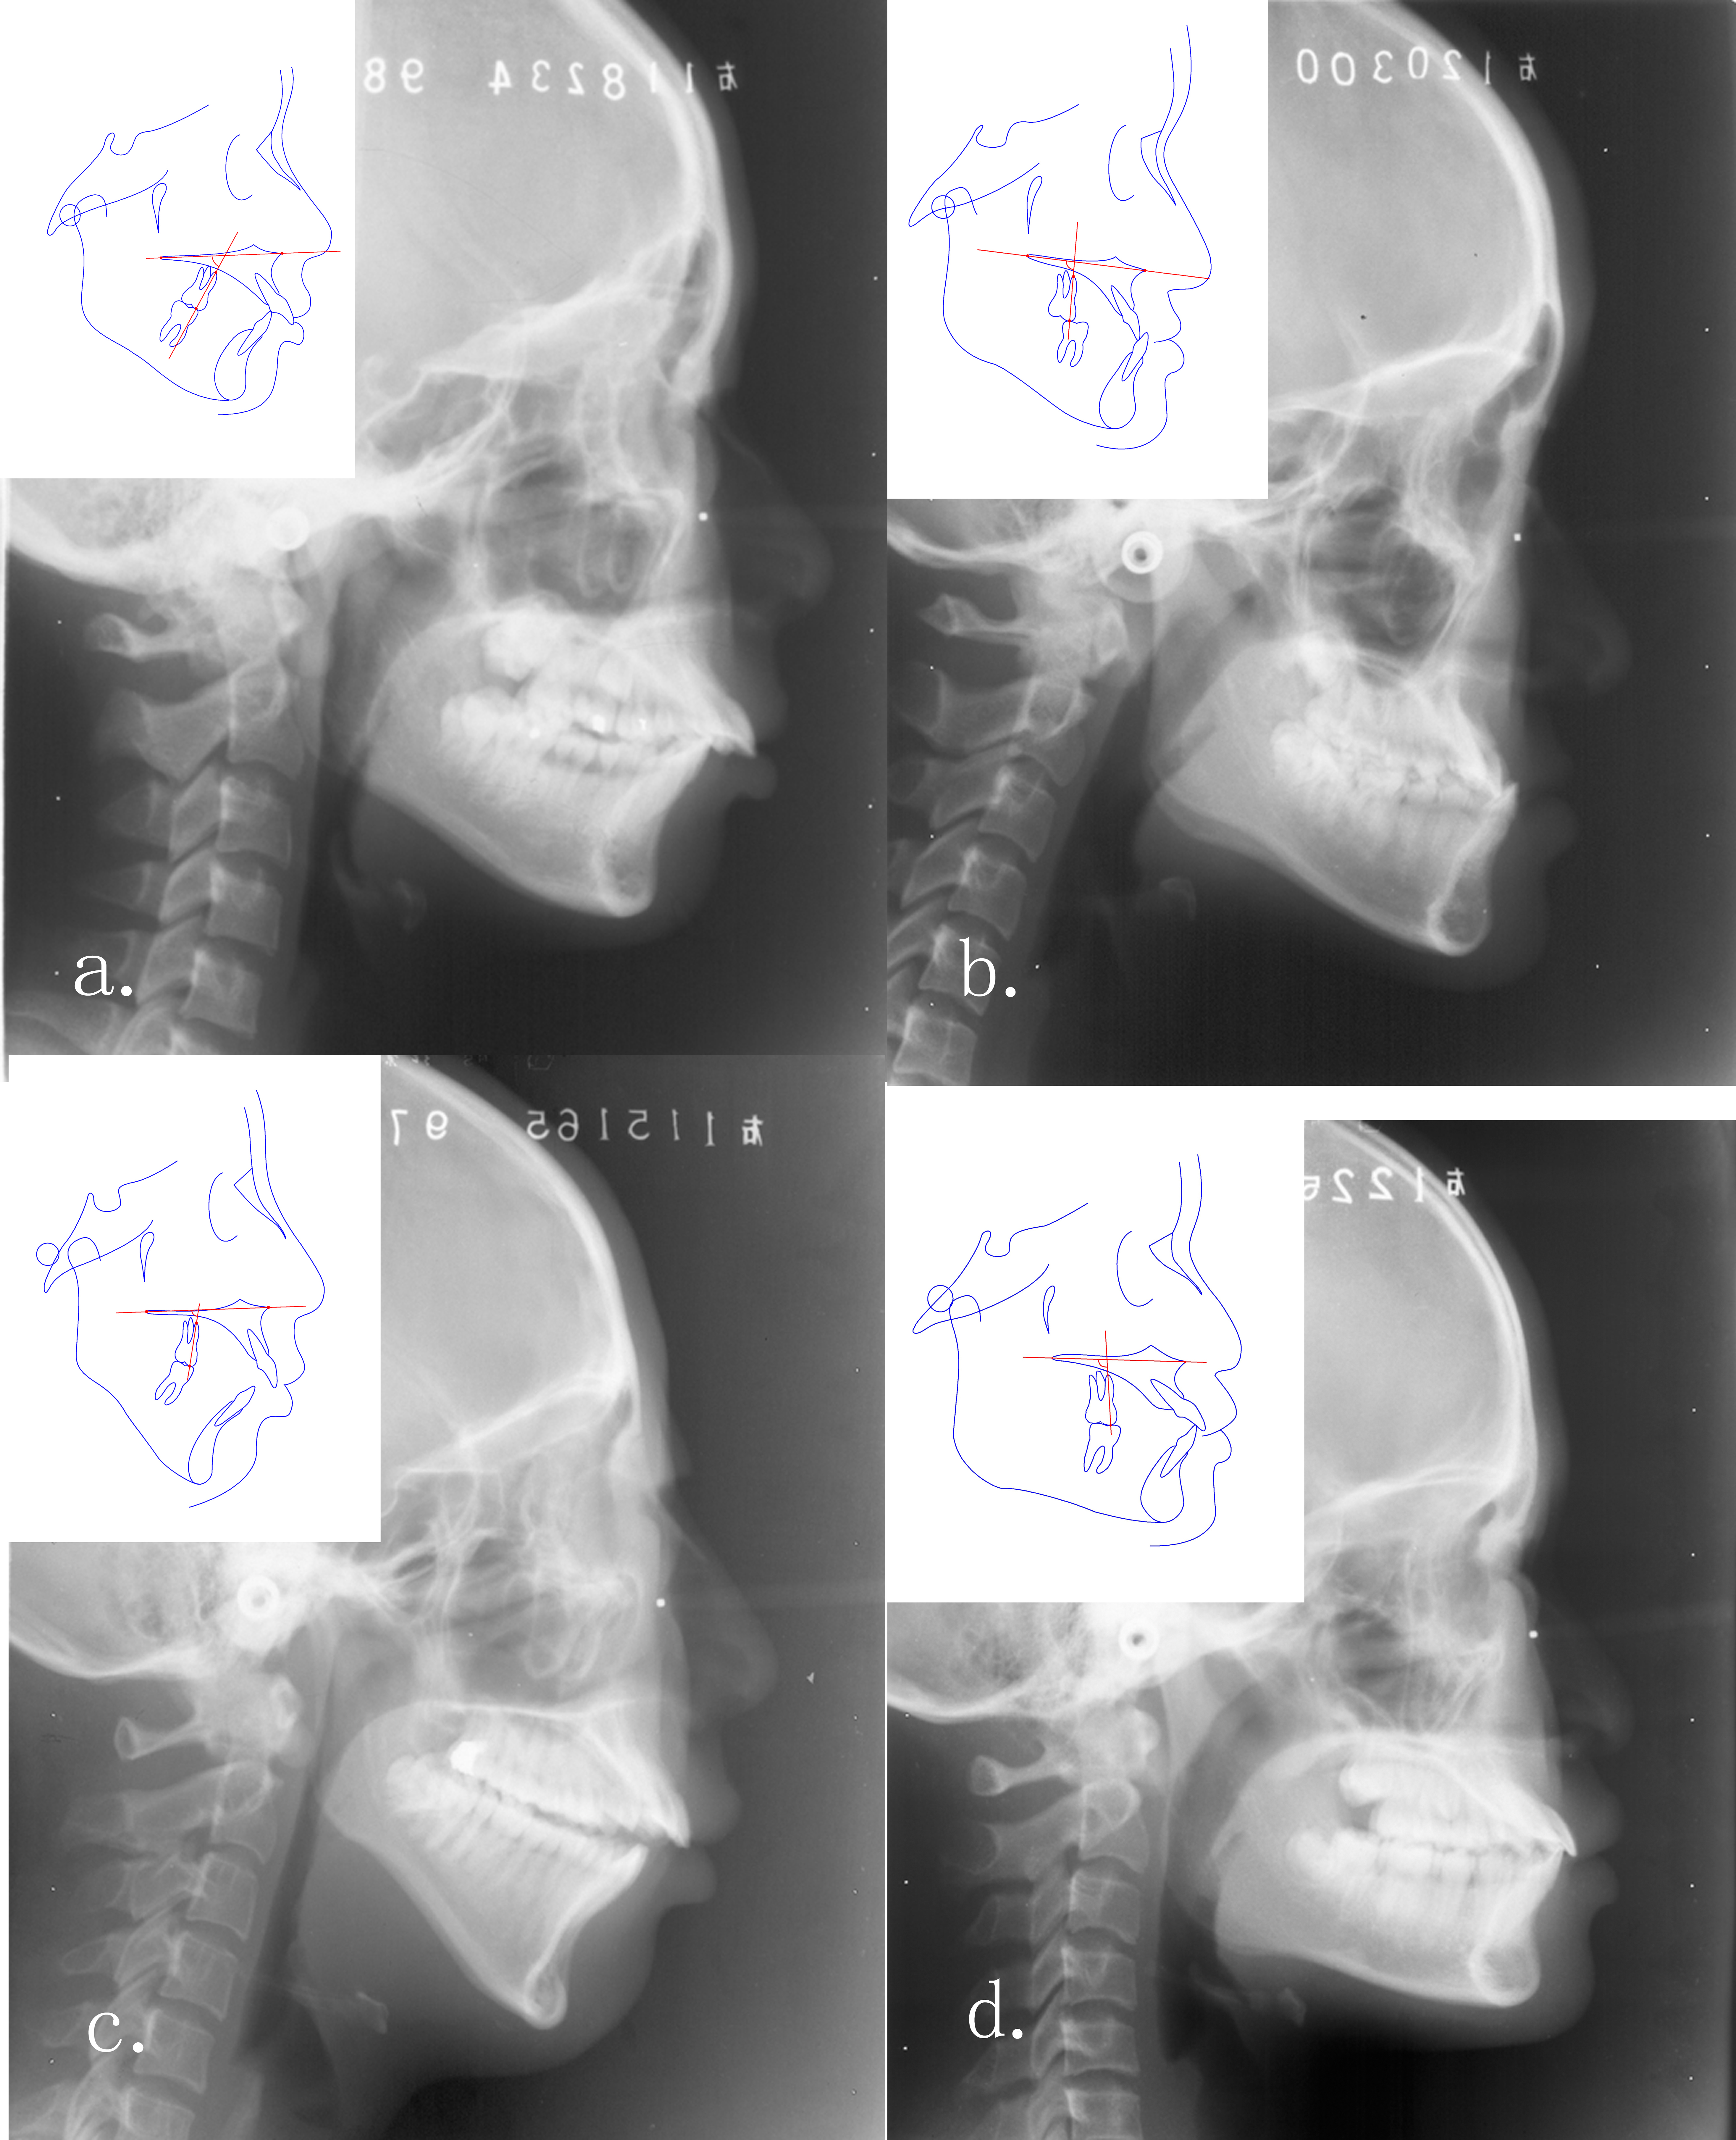

Objectives: We investigated the compensatory trends of mesiodistal angulation of the first molars in 1,403 malocclusion cases to compare the differences in angulation of the first molars among cross-sections in different developmental stages, malocclusion classifications and skeletal patterns.

Methods: The medical records and lateral cephalograms of 1,403 malocclusion cases taken before treatment were measured to evaluate compensation of molar angulation in relation to the skeletal jaw. Cases were stratified by age, angle classification, and skeletal patterns. Differences in mesiodistal angulation of the first molars were compared among the stratifications.

Results: We observed three main phenomena. First, the angulation of the upper first molar varied significantly with age, and tipped most distally in cases aged <12 years and least distally in cases aged >16 years. The lower first molar did not show these differences. Second, in Angle Class II or skeletal class II cases, the upper first molar was the most distally tipped, the lower first molar was the most mesially tipped, and opposite angulation compensation was observed in Class III cases. Third, in high-angle cases, the upper and lower first molars were the most distally tipped, and opposite angulation compensation was observed in low-angle cases.

Conclusions: These data suggest that the angulation of molars had compensations for various growth patterns and malocclusion types and awareness of molar angulation compensation would help to adjust occlusal relationship, control anchorage, and increase the chances of long-term stability.